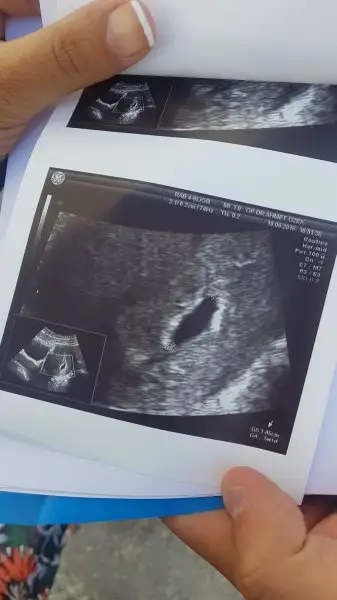

Benim 17 eylülde 6+1. Boyu 14 mm di. Haftasıyla uyumlu dedi. Beta ya bakmadı. Tahminimce 7000 lerdeydi benimde.bu kese 19 eylül tarihine ait. yani 5 gün önce. 1.05 cm. doktorun deyimi ile 10.5 mm. 18 eylül tarihli kan değerim de 6884.97

Benimkide böyleydi. Sizin bu resimde ne kadarlıksınız. Birde kese boyu kaç mmkese görünümünüz nasıl. benim ilk 4 haftalıkken yusyuvarlaktı 5.hafta da ince uzun şekle girmişti. doktor bişi demedi sağlıklı gebelik dedi kan pıhtıları filan yok dedi. kese rahim de oluşmuş dedi. dış gebelik vs değil dedi. kalp atışı için haftaya gelin dedi ama yine de internetten baktığımda herkesin kesesi yuvarlak.

Benim de buna benzer sadece biraz daha büyük ama benim ultrasonda bebek daha büyük çıktı. Endişe yapma herkesin farklı olabilir ne güzel söylemiş işte doktor, bu hafta git canım göremezsen haftaya gidersin. Endişe etme.kese görünümünüz nasıl. benim ilk 4 haftalıkken yusyuvarlaktı 5.hafta da ince uzun şekle girmişti. doktor bişi demedi sağlıklı gebelik dedi kan pıhtıları filan yok dedi. kese rahim de oluşmuş dedi. dış gebelik vs değil dedi. kalp atışı için haftaya gelin dedi ama yine de internetten baktığımda herkesin kesesi yuvarlak.